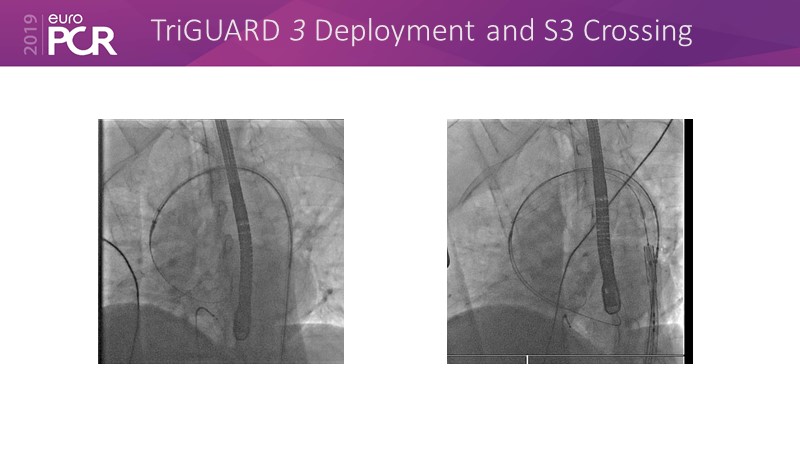

Consult this session to hear the latest update on the US REFLECT phase II trial, to learn about the EU experience with the TriGUARD 3 CEP device and to learn about Keystone Heart's EU roadmap.

- To learn about the EU experience with the TriGUARD 3 CEP device